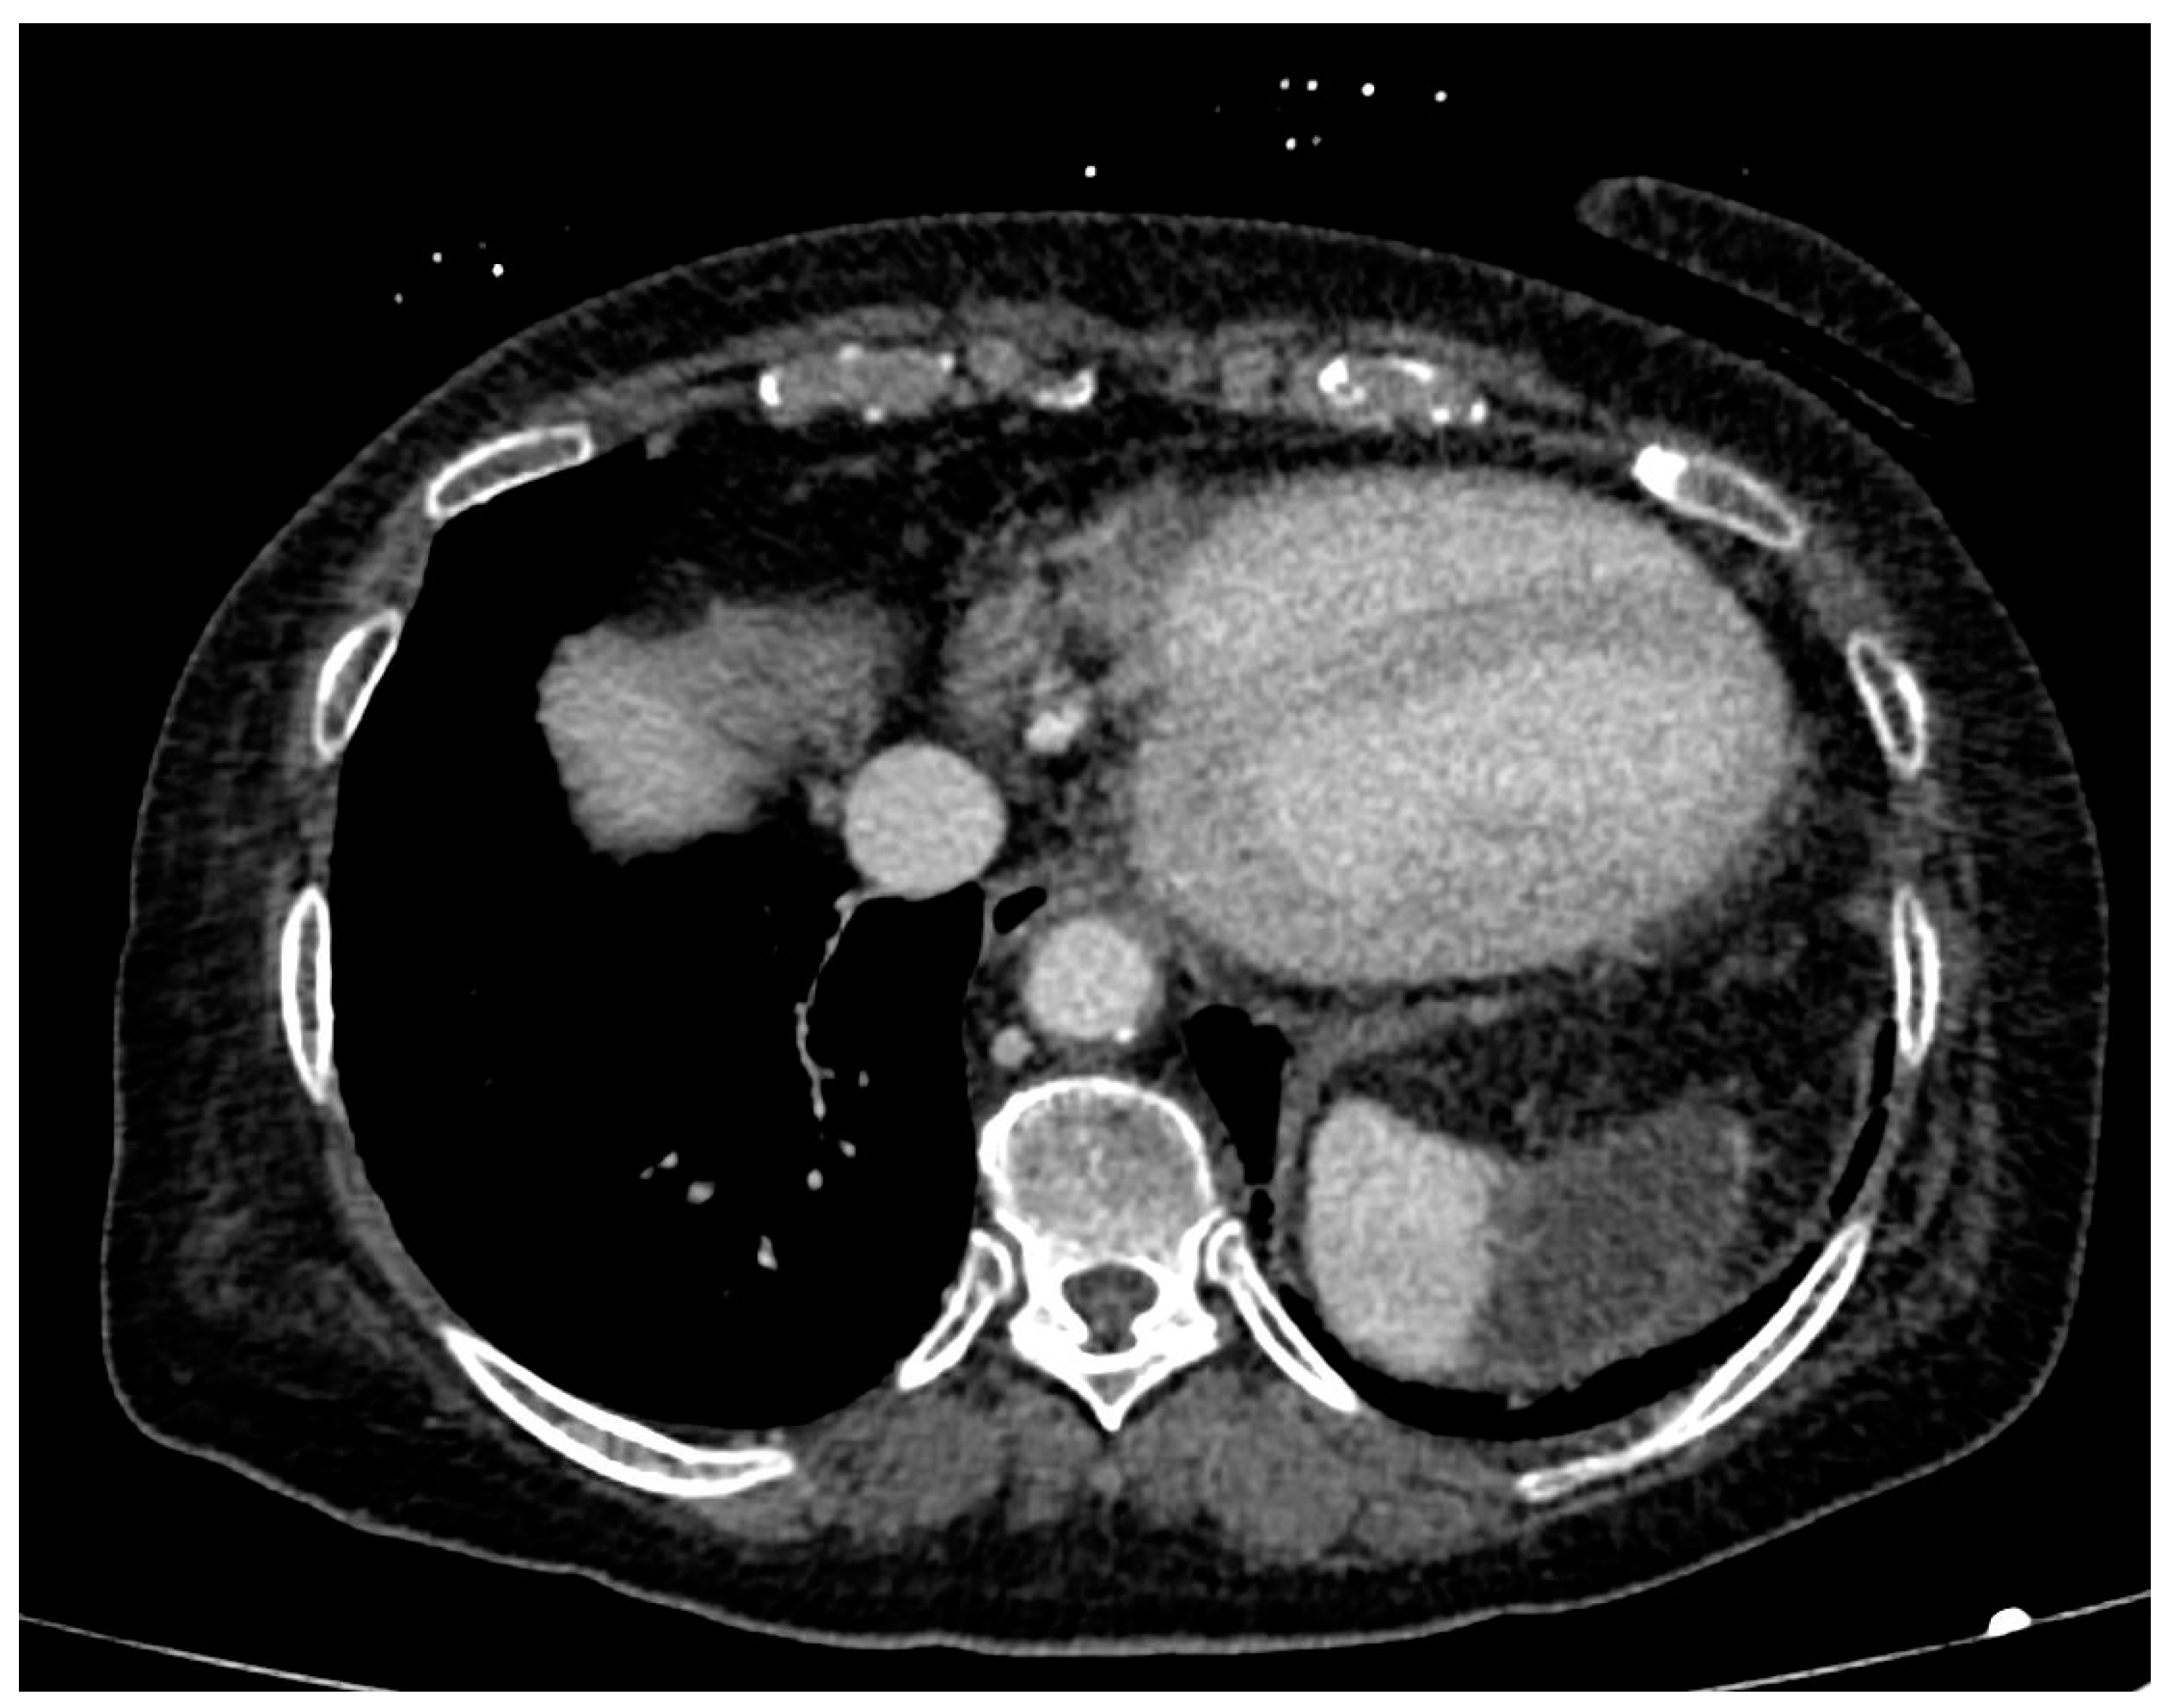

- In one case (9.1%), hypoperfusion of the intestinal loops was evidenced due to extensive thrombosis of the superior mesenteric artery (Figure 5); this patient was the one with predominant abdominal pain symptoms.